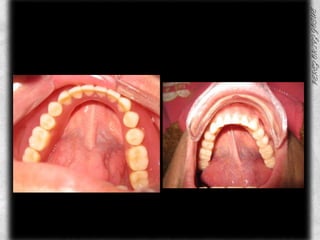

ARCADA SUPERIOR CLASIFICACIÓN DE OSAWA TIPO IFORMA DE PROCESO “U”LINEA MEDIA COINCIDE CON EL RAFE PALATINOCOLOR ROJO BRILLANTETEXTURA LISAPROCESO ALVEOLAR TIPO IAPARENTEMENTE SIN PRESENCIA DE CANDIDABUENA INSERCION DE LOS FRENILLOS

ARCADA INFERIORSIN PRESENCIA DE ORGANOS DENTARIOSCOLORACION ROSABUENA INSERCION DEL FRENILLO LINGUAL PROCESO ALVEOLAR TIPO IIISIN PRESENCIA DE CANDIDASIN ULCERACIONES